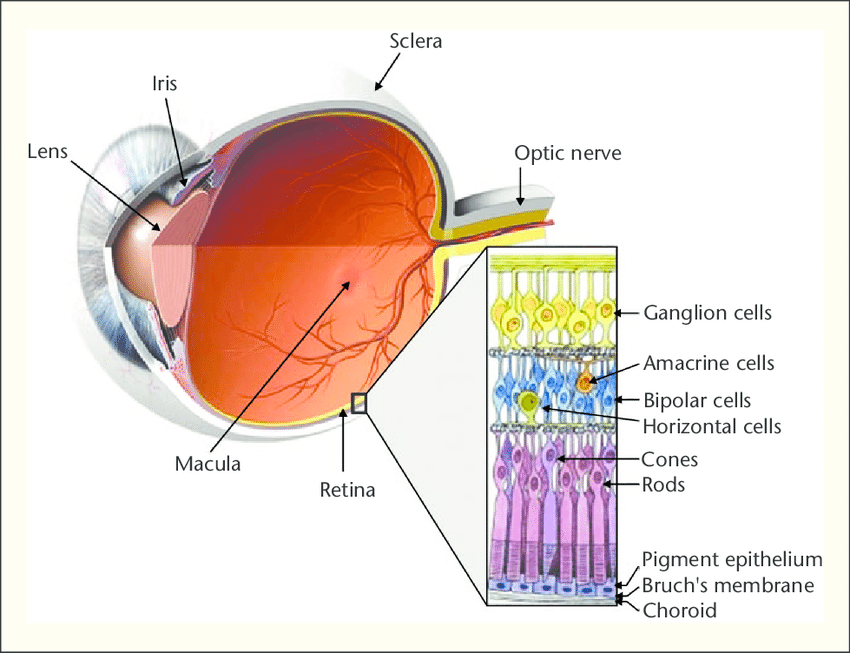

The human eye can be compared with the device of the camera, the lens of which is the cornea with the lens, and the film is the retina, an extremely complex multi-layer structure that is connected to the visual divisions of the brain with the help of nerve fibers. Therefore, we can assume that the retina is a part of the brain.

可以将人眼与摄像头的设备进行比较,摄像头的透镜是角膜和透镜,而胶片是视网膜,这是一种极其复杂的多层结构,通过眼睛与大脑的视觉区域相连。帮助神经纤维。 因此,我们可以假设视网膜是大脑的一部分。

Detachment is the separation of rods and cones, we call them neuroepithelium, from the underlying pigment epithelium by the accumulation of fluid between them. This disrupts the power of the outer layers of the retina, which leads to rapid loss of vision.

分离是棒和视锥的分离,我们称它们为神经上皮,是通过它们之间的积聚而从下面的色素上皮中分离出来的。 这会破坏视网膜外层的力量,从而导致视力Swift丧失。

The eye, as you know, has the shape of a sphere, and we already know that it has a lens, a retina film, besides this, inside the eye is filled with liquids. These fluids are almost 98-99% water, but with very substantial additives. The anterior part of the eye is bounded by the cornea on one side and the iris-lens block on the other. This part of the eye is more responsible for optics and is filled with anterior chamber intraocular fluid. In terms of its properties and appearance, it hardly differs from simple water with the addition of a complex set of minerals and salts.

如您所知,眼睛具有球体的形状,而且我们已经知道它具有晶状体,即视网膜膜,此外,眼睛内部充满了液体。 这些流体几乎是98-99%的水,但含有非常大量的添加剂。 眼睛的前部在一侧被角膜所包围,而在另一侧则被虹膜透镜所阻挡。 眼睛的这一部分负责光学,并充满前房眼内液。 就其性质和外观而言,它与简单的水几乎没有什么不同,只是添加了一组复杂的矿物质和盐。

Another thing is the fluid in the posterior part, bounded by the lens, ciliary body and retina. This liquid is called the vitreous body, it has the consistency and the appearance of a gel or frozen jelly. In addition, the basis of the vitreous body is a framework in the form of a voluminous lattice of collagen fibers.

另一件事是后部的液体,以晶状体,睫状体和视网膜为界。 这种液体称为玻璃体,具有凝胶状或冻冻状的稠度和外观。 另外,玻璃体的基础是胶原纤维的大量格子形式的框架。